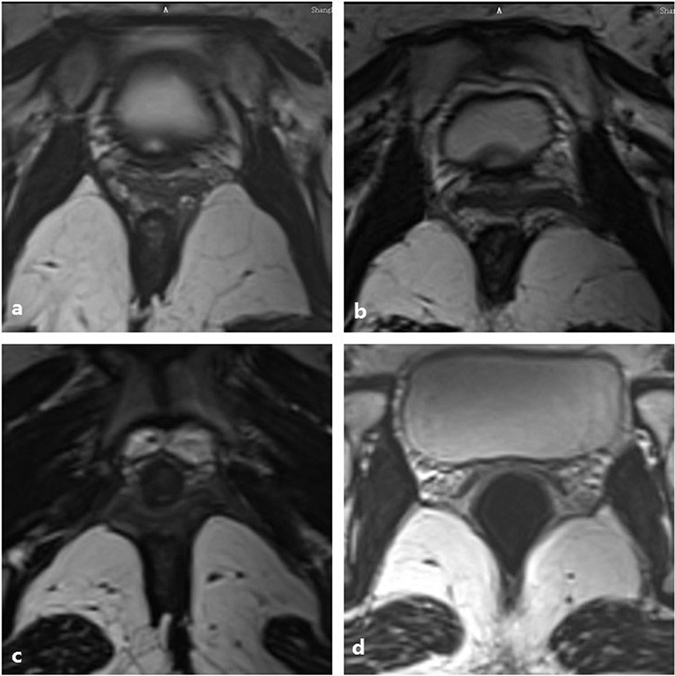

Figure 4.

(a) Reveals that the left part of the iliococcygeus muscle fibre become thin without obvious avulsion. No defect is found on the right side. (b) Shows that the left iliococcygeus muscle became thin and detached from the arcus tendinous levator ani that overlies the obturator internus muscle. (c) Shows the left avulsion with the obturator muscle injury and an abnormal signal inserted into their connection. (d) Shows that bilateral iliococcygeus muscles became thin. The left side muscle defected in the middle part without fracture, similar to a greenstick fracture.

The levator ani muscle can be distinguished as the puborectalis and iliococcygeus on MRI. Moreover, the levator ani muscle can be observed in the axial, coronal and sagittal planes (Fig. 3). The puborectalis originates from the inner surface of the pubic bone and runs dorsal to the rectum as a sling (Fig. 3a). The MRI results demonstrated that puborectalis avulsions occurred on the left (n = 4), on the right (n = 4) or bilaterally (n = 3). The iliococcygeus originates from the arcus tendinous levator ani (ATLA), which overlies the obturator internus muscle, bypassing the rectum to the ATLA on the other side (Fig. 3b). In the coronal plane, it was similar to a wing (Fig. 3c). When the wing-like morphology disappeared, damage to the iliococcygeus should be assessed. The sagittal images also showed the orientation of the iliococcygeus muscle (Fig. 3d). On the MRIs, the morphological changes of the iliococcygeus could be well-observed (Fig. 4); it became thin but was still attached to the ATLA (n = 6) (Fig. 4a) or deficient in the middle without avulsion (n = 2) (Fig. 4d), detaching from the ATLA with an obturator muscle injury (n = 2) (Fig. 4b) or without an obturator muscle injury (n = 3) (Fig. 4c).

Due to its superior discriminatory capabilities, pelvic MRI has been becoming more popular recently. MRI can show the details of the levator ani muscle and display the different components of the levator ani muscle. Furthermore, a 3D MRI-based model can provide more details about the levator ani muscle. It provides a tomographic overview to observe the stereoscopic levator complex and shows more details of the puborectalis and iliococcygeus muscle at their origin and insertion22. The detection of either the minor avulsion or full avulsion using 3D MRI is much more sensitive than 3D ultrasound. In this study, ultrasound images of 11 postpartum women showed left avulsion of the puborectalis muscle in 4 cases, right avulsion in 4 cases, and bilateral avulsion in 3 cases. One of them, who was diagnosed with only left avulsion on ultrasound, showed complete avulsion on both sides on MRI. The consistency of diagnosing puborectalis avulsion between ultrasound and MRI is good. However, it is difficult to observe the iliococcygeus on ultrasound. Due to the wider range of inspection and good soft tissue resolution of MRI, it can complement the lack of ultrasound in this regard. Bilateral iliococcygeus lesions were also recorded separately. The MRI results showed that iliococcygeus muscle injuries could be expressed as becoming thinner (n = 6). The iliococcygeus muscle was separated from the TALA in 5 patients, and injury of the obturator muscle was found in 2 patients. In 2 patients, the iliococcygeus muscle are deficient in the middle part without obvious avulsion, similar to a ‘greenstick fracture’. However, all iliococcygeus muscle injuries occurred on the ipsilateral side of the puborectalis muscle that was gravely damaged. Accordingly, when the puborectalis muscle was not obviously abnormal, the ipsilateral iliococcygeus muscle was also normal. Therefore, in routine clinical work, ultrasound has rapid and convenient advantages to examine postpartum women. However, we recommend that if a patient is found to have a severe injury of the puborectalis, it is necessary to perform an MRI examination to rule out iliococcygeus muscle injuries.